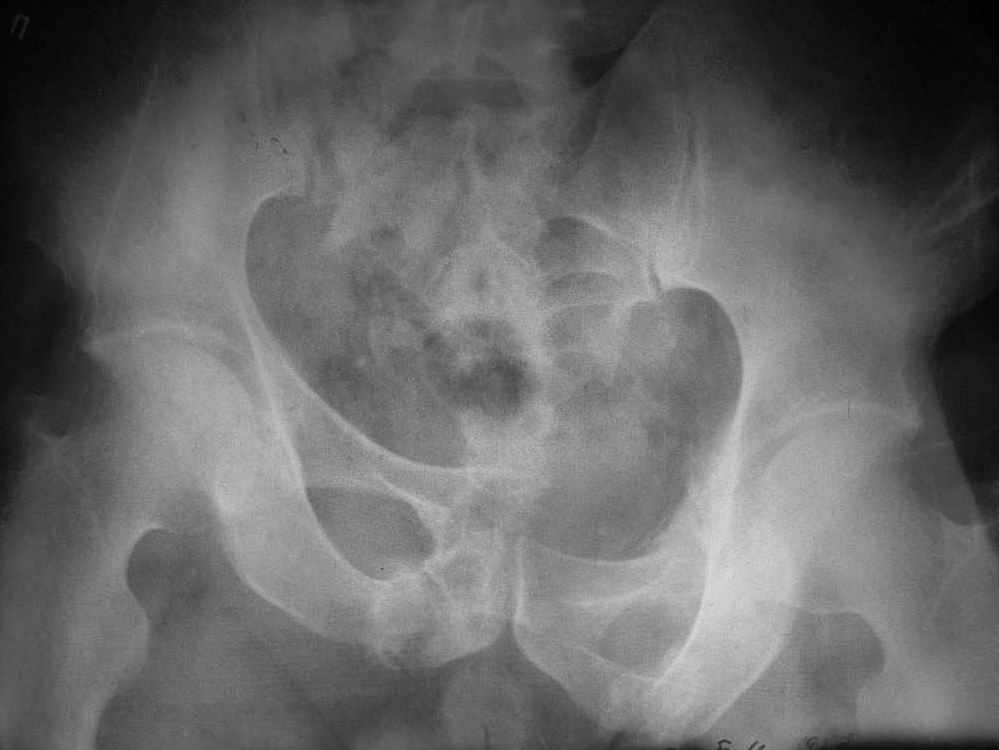

По прямой проекции - Вертикальная стабильная (?) деформация таза IIIст., неправильно сросшийся (?) перелом боковой массы крестца справа, неправильно сросшийся поперечный (?) перелом првавой вертлужной впадины.

Пример лечения стабильной деформации с вертикальным смещением половины таза.

Исходная картина